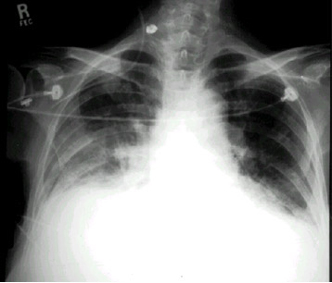

Bei diesem Patienten hat der Chirurg nicht nur auf die obligatorische Durchleuchtng verzichtet, sondern auch noch die ganzen 50 cm Plastikschlauch, die in der Packung sind, ungekürzt in den Patienten geschoben, obwohl der Abstand von der Punktionsstelle bis zur Cava/Vorhofgrenze, wo die Katheterspitze liegen soll, nur 10-12 cm beträgt. Dem Patienten wurden mehrere Zyklen Chemotherapie ins Hirn infundiert, bis die resultierende Sinusvenenthrombose zur Entdeckung der Fehllage führte.